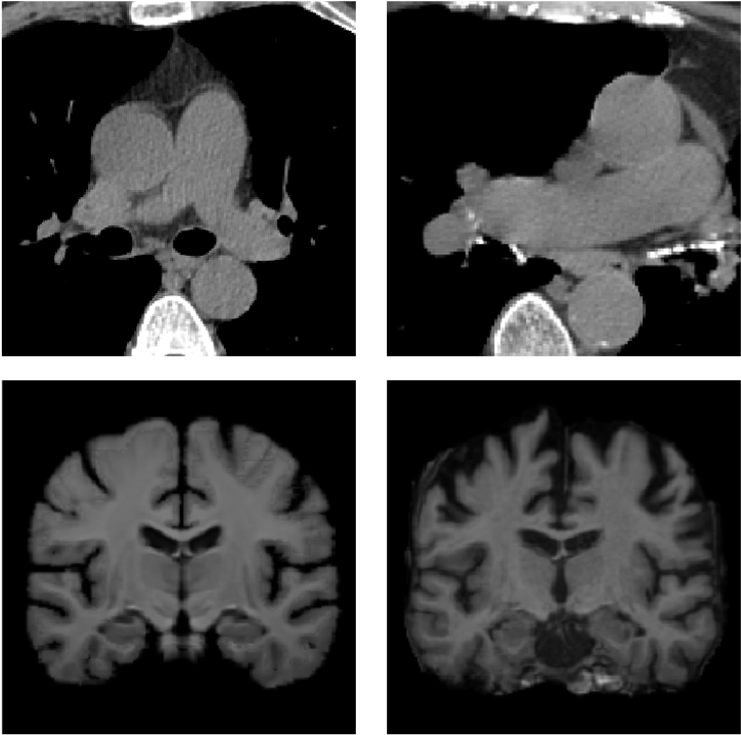

TABLE V: Visualization result on SegTHOR. Gray image registration result(row 1-2) shows the fitting ability of various methods. Mask image registration result(row 3-4) shows the regional continuity of various methods. The mask includes four parts: heart(green), aorta(yellow), trachea(blue) and esophagus(red).

[Uncaptioned image] [Uncaptioned image] [Uncaptioned image] [Uncaptioned image] [Uncaptioned image] [Uncaptioned image]

F M VoxelMorph Ants deedsBCV Ours

We selected four images of large deformations occurring at different locations from different CT, the visualization results are shown in Table V.

Rows 1-2 shows the CT gray image registration results. The task is to register MM to FF. From the visualization of gray image results, we can see that although ANTs and deedsBCV has high dice scores, the visualization results look unrealistic. Meanwhile, deep learning methods look smoother. The sixth column shows the results of our method. The fitting effect is improved compared to previous methods.

Rows 3-4 shows the mask registration results. The background of each image is FF. We could judge the performance by observing the fitting degree of the mask and background. In many practical tasks, we use a registration algorithm to register MM’mask to get the mask of FF. There may be a situation where the gray image fitting is good, but the mask result is poor. This may be because the continuity of the registration field is not good enough.